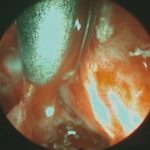

679

'25年10月

30代

聴神経腫瘍

頭蓋内腫瘍摘出術

No.’25_81 手術前1

No.’25_81 手術前2

No.’25_81 摘出 前

No.’25_81  摘出 中

No.’25_81 摘出 後